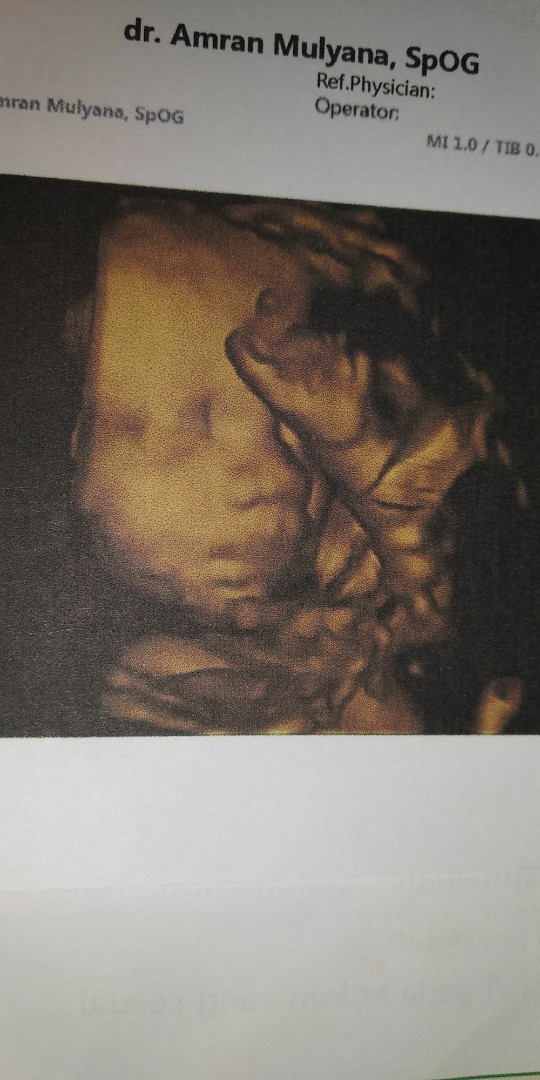

USG

Bunda barusan aku beres USG ini dedenya lagi cemberut ? dan alhamdulillah semuanya normal tapi hpl nya malah mundur seminggu yang tadinya 22 oktober jadi 29 oktober, tapi kalo hitungan bidan sama di aplikasi hamil sama sekarang usia kandungan 33w dan hplnya 22 oktober paling akhir, adakah yang sama sperti aku hpl di USG jadi mundur??